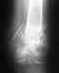

несрастающийся перелом ключицы у девочки 3,5лет

Здравствуйте. У дочки перелом правой ключицы со смещением.

В трамбольнице 16 февраля была наложена повязка из бинта. А 18 февраля наложили гипс (форма восьмерки ). В гипсе дочка проходила 3,5 недели . В течении этого времени смещения нестало.По срокам гипс должны были снять 12 марта- нам его сняли,сделали контрольный снимок.Снимок показал ,что образовавшаяся мозоль в месте перелома слишком тонкая,а сам перелом не сросся.В результате снова наложили гипс еще на 2 недели,еще назначили УВЧ №7. Врач физиолог сказал когда мы пришли к нему с направлением ,что обычно УВЧ назначают на ранних сроках,а в нашем случае т.к прошло 3,5 недели нужно делать электрофорез с раствором кальция хлорида 2%. Мы согласились на электрофорез.ВОПРОС: скажите пожалуйста , может ли ключица не срастаться если был неправильно наложен гипс.И как нам быть дальше? Заранее спасибо.